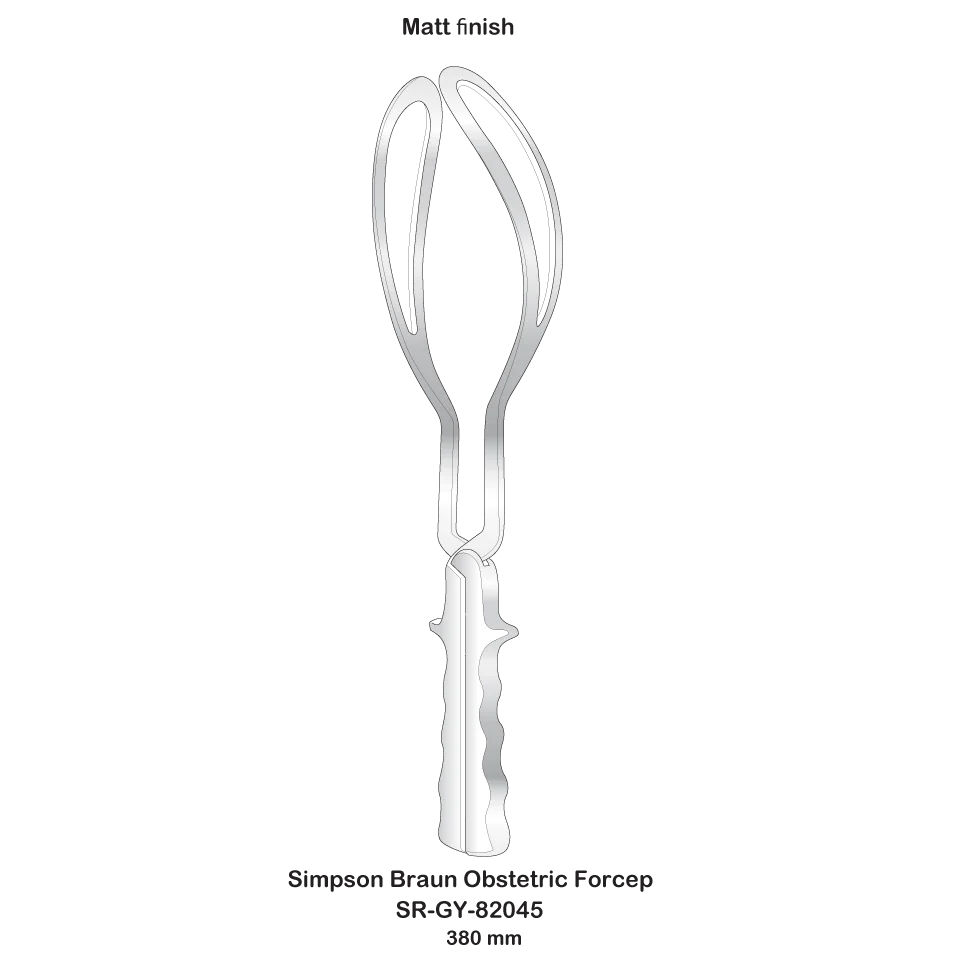

Simpson Obstetric Forceps gynecological instruments high quality surgical instruments

- Category:

- Supplier: SURGI,RANGE,CORPORATION

In Stock